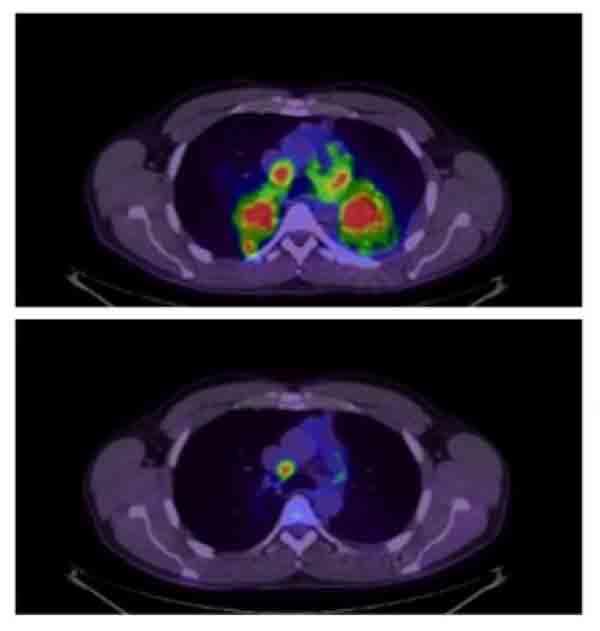

Before and after PET scan of patient treated with crizotinib.

In patients with non-small cell lung cancer whose tumors have alterations in the ALK gene, ALK-inhibitors like brigatinib and crizotinib can dramatically shrink tumors.

Credit: J Pers Med April 2012. CC BY 3.0.